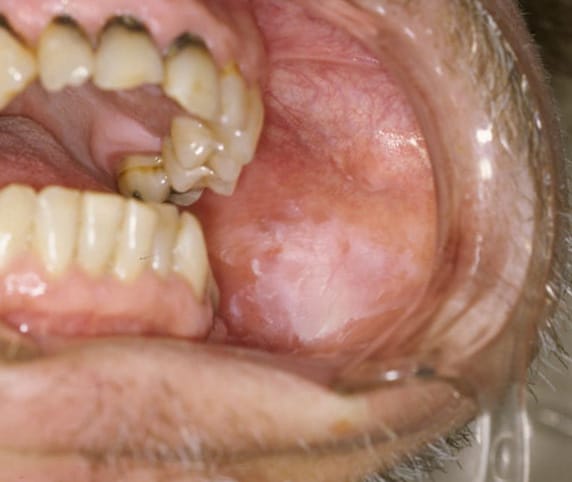

Clinically, oral leukoplakia appears as a white lesion that can have a wrinkled or “dry, cracked mud” surface appearance (see image 1).5 The areas where these lesions can most commonly be found are the buccal mucosa, both the hard and soft palates, lateral borders, and ventral surface of the tongue.5